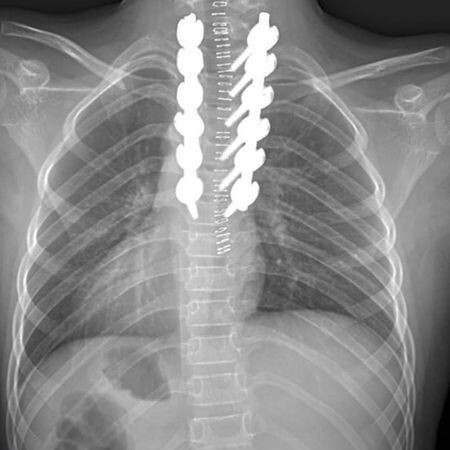

Мальчик сломал позвоночник во время катания на "ватрушке". На ноги его поставили врачи Новосибирского НИИТО. 9-летний Даниэль не смог затормозить и врезался в дерево. Диагноз — перелом грудного позвонка. Родители обратились в травмпункт, оттуда их отправили в горбольницу №1, а после обследований — в НИИ. Здесь ребёнку установили металлическую конструкцию. Её уберут, когда придёт время. Школьнику уже лучше, его выписали. Может сам вставать и с помощью папы ходить на небольшие расстояния. На прощание Даниэль сказал врачам, что больше не будет гонять на "ватрушке". Пока ему придётся посидеть на домашнем обучении.

9-летний Даниэль не смог затормозить и врезался в дерево. Диагноз — перелом грудного позвонка. Родители обратились в травмпункт, оттуда их отправили в горбольницу №1, а после обследований — в НИИ. Здесь ребёнку установили металлическую конструкцию. Её уберут, когда придёт время.